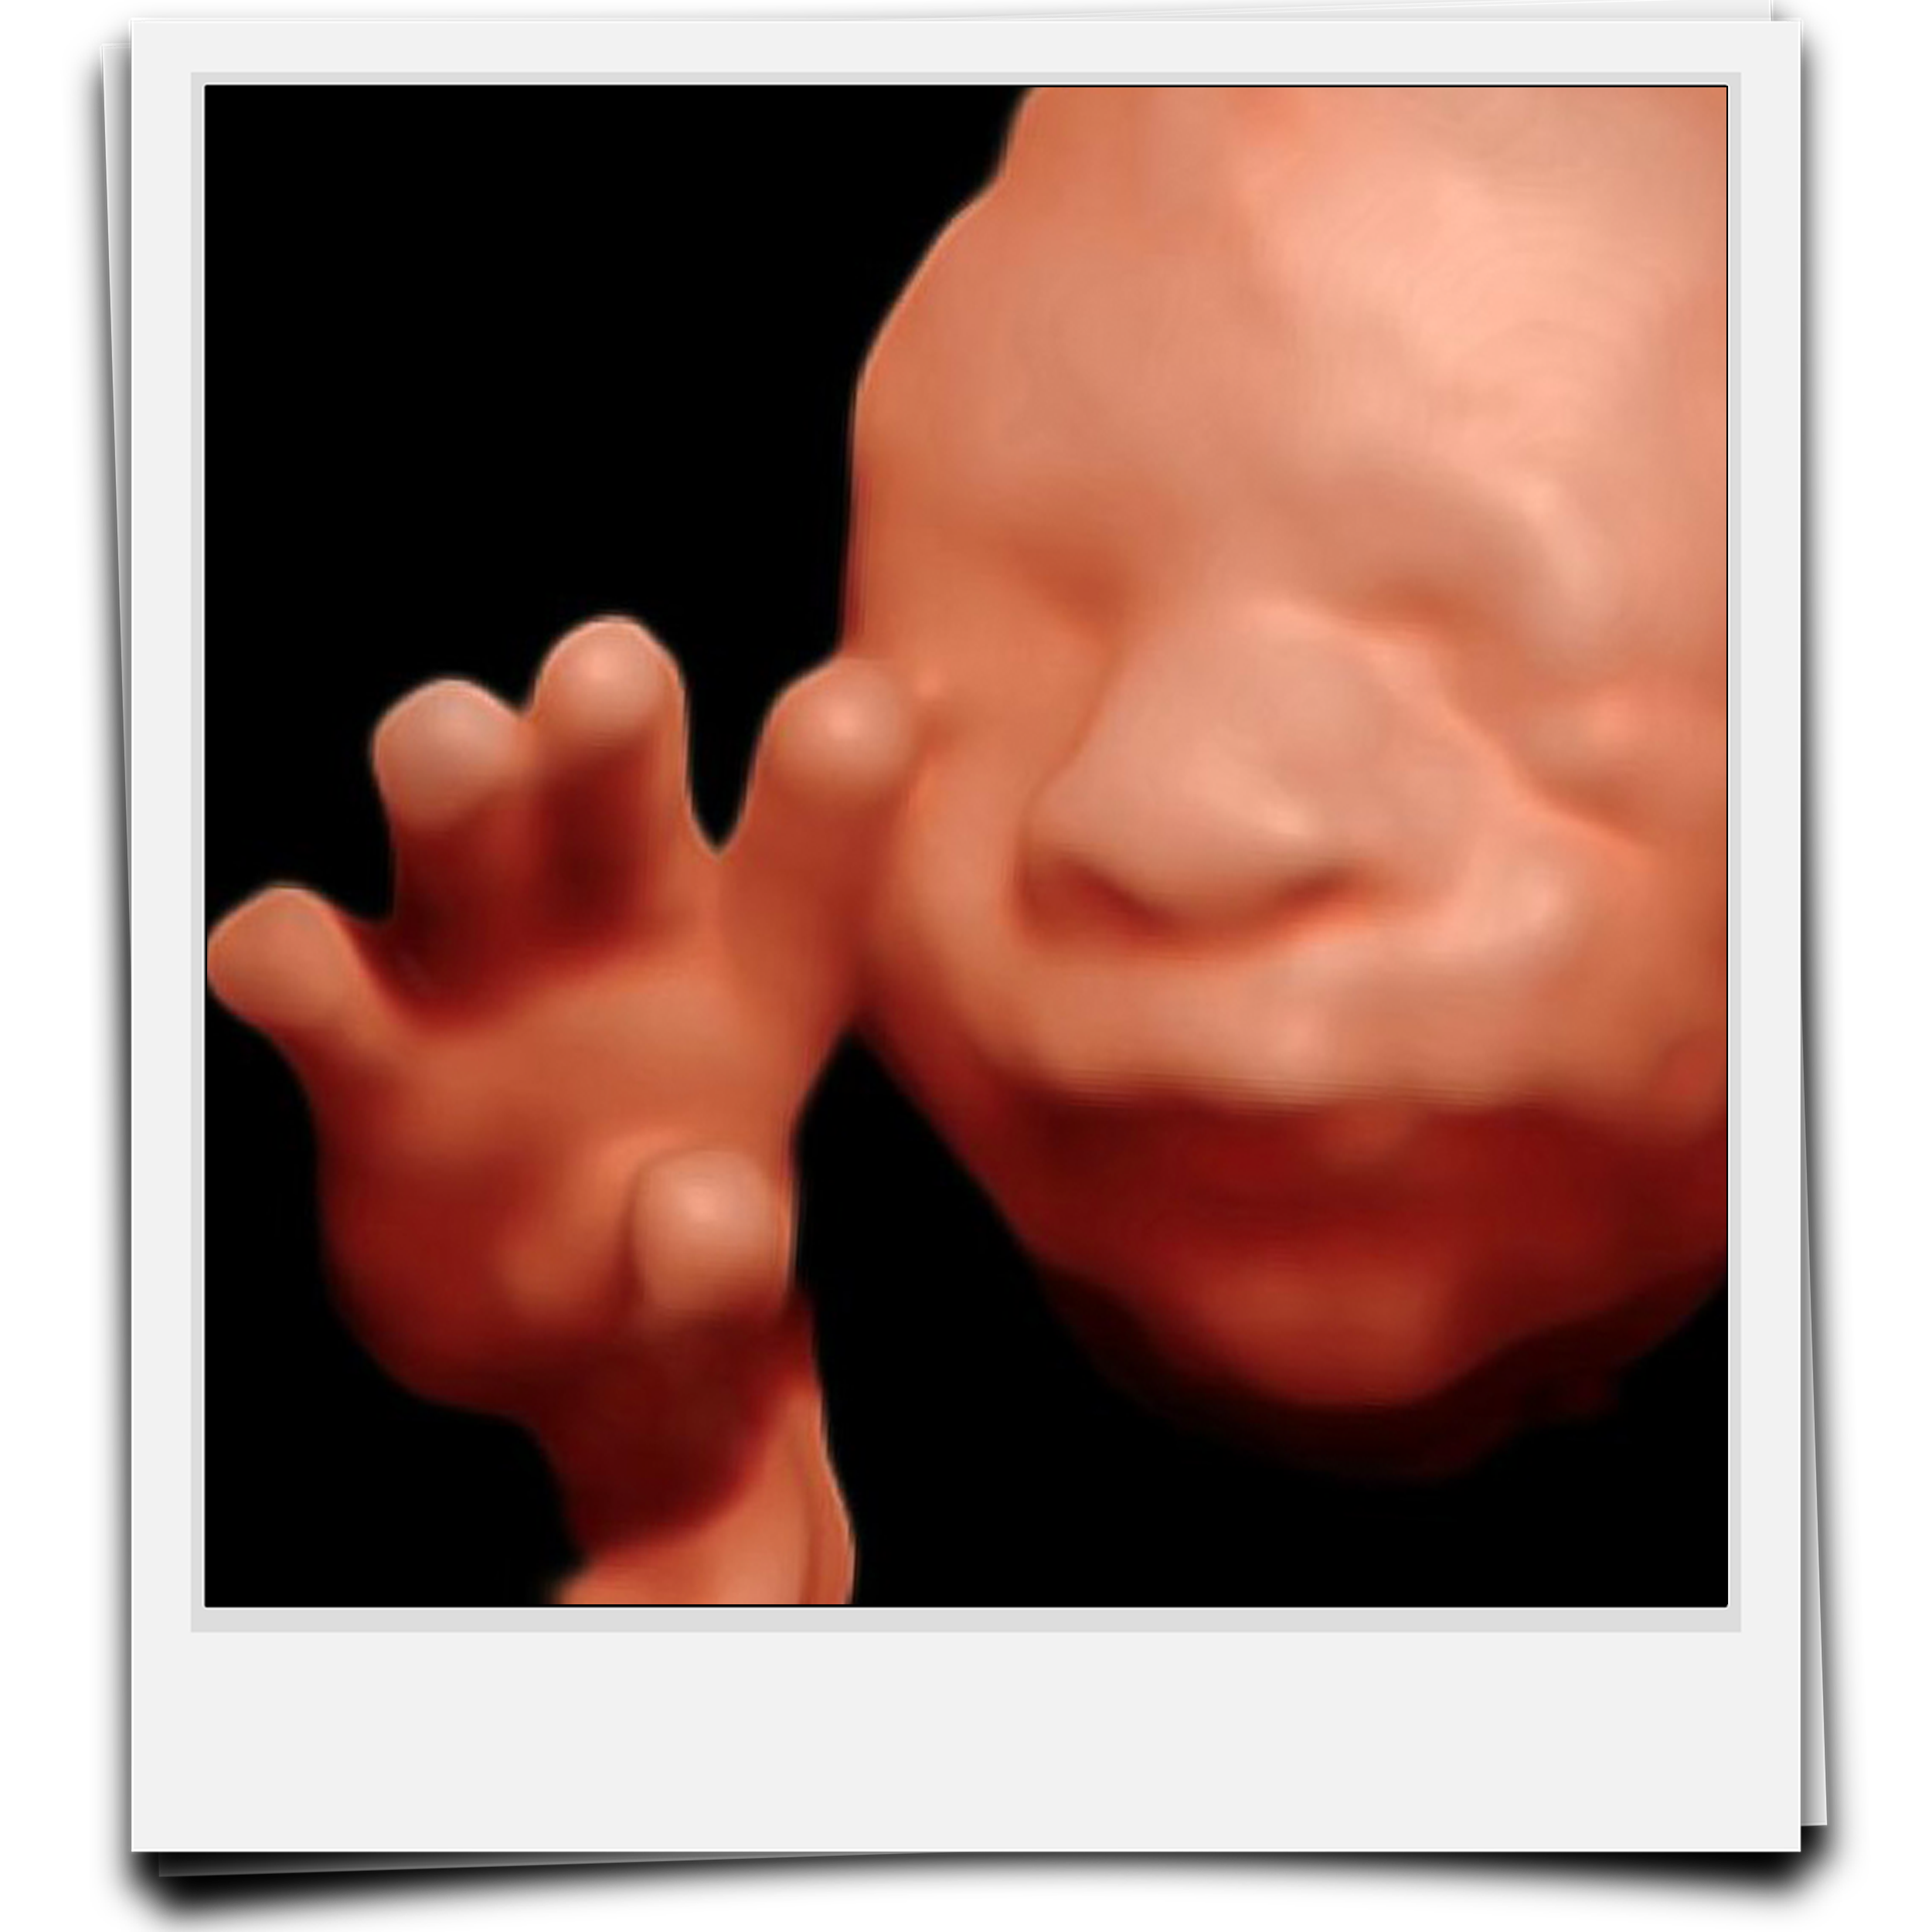

Ultrasonidos 4D y 5D

Ultrasonido 5D

¡Ven a conocer al amor de tu vida!